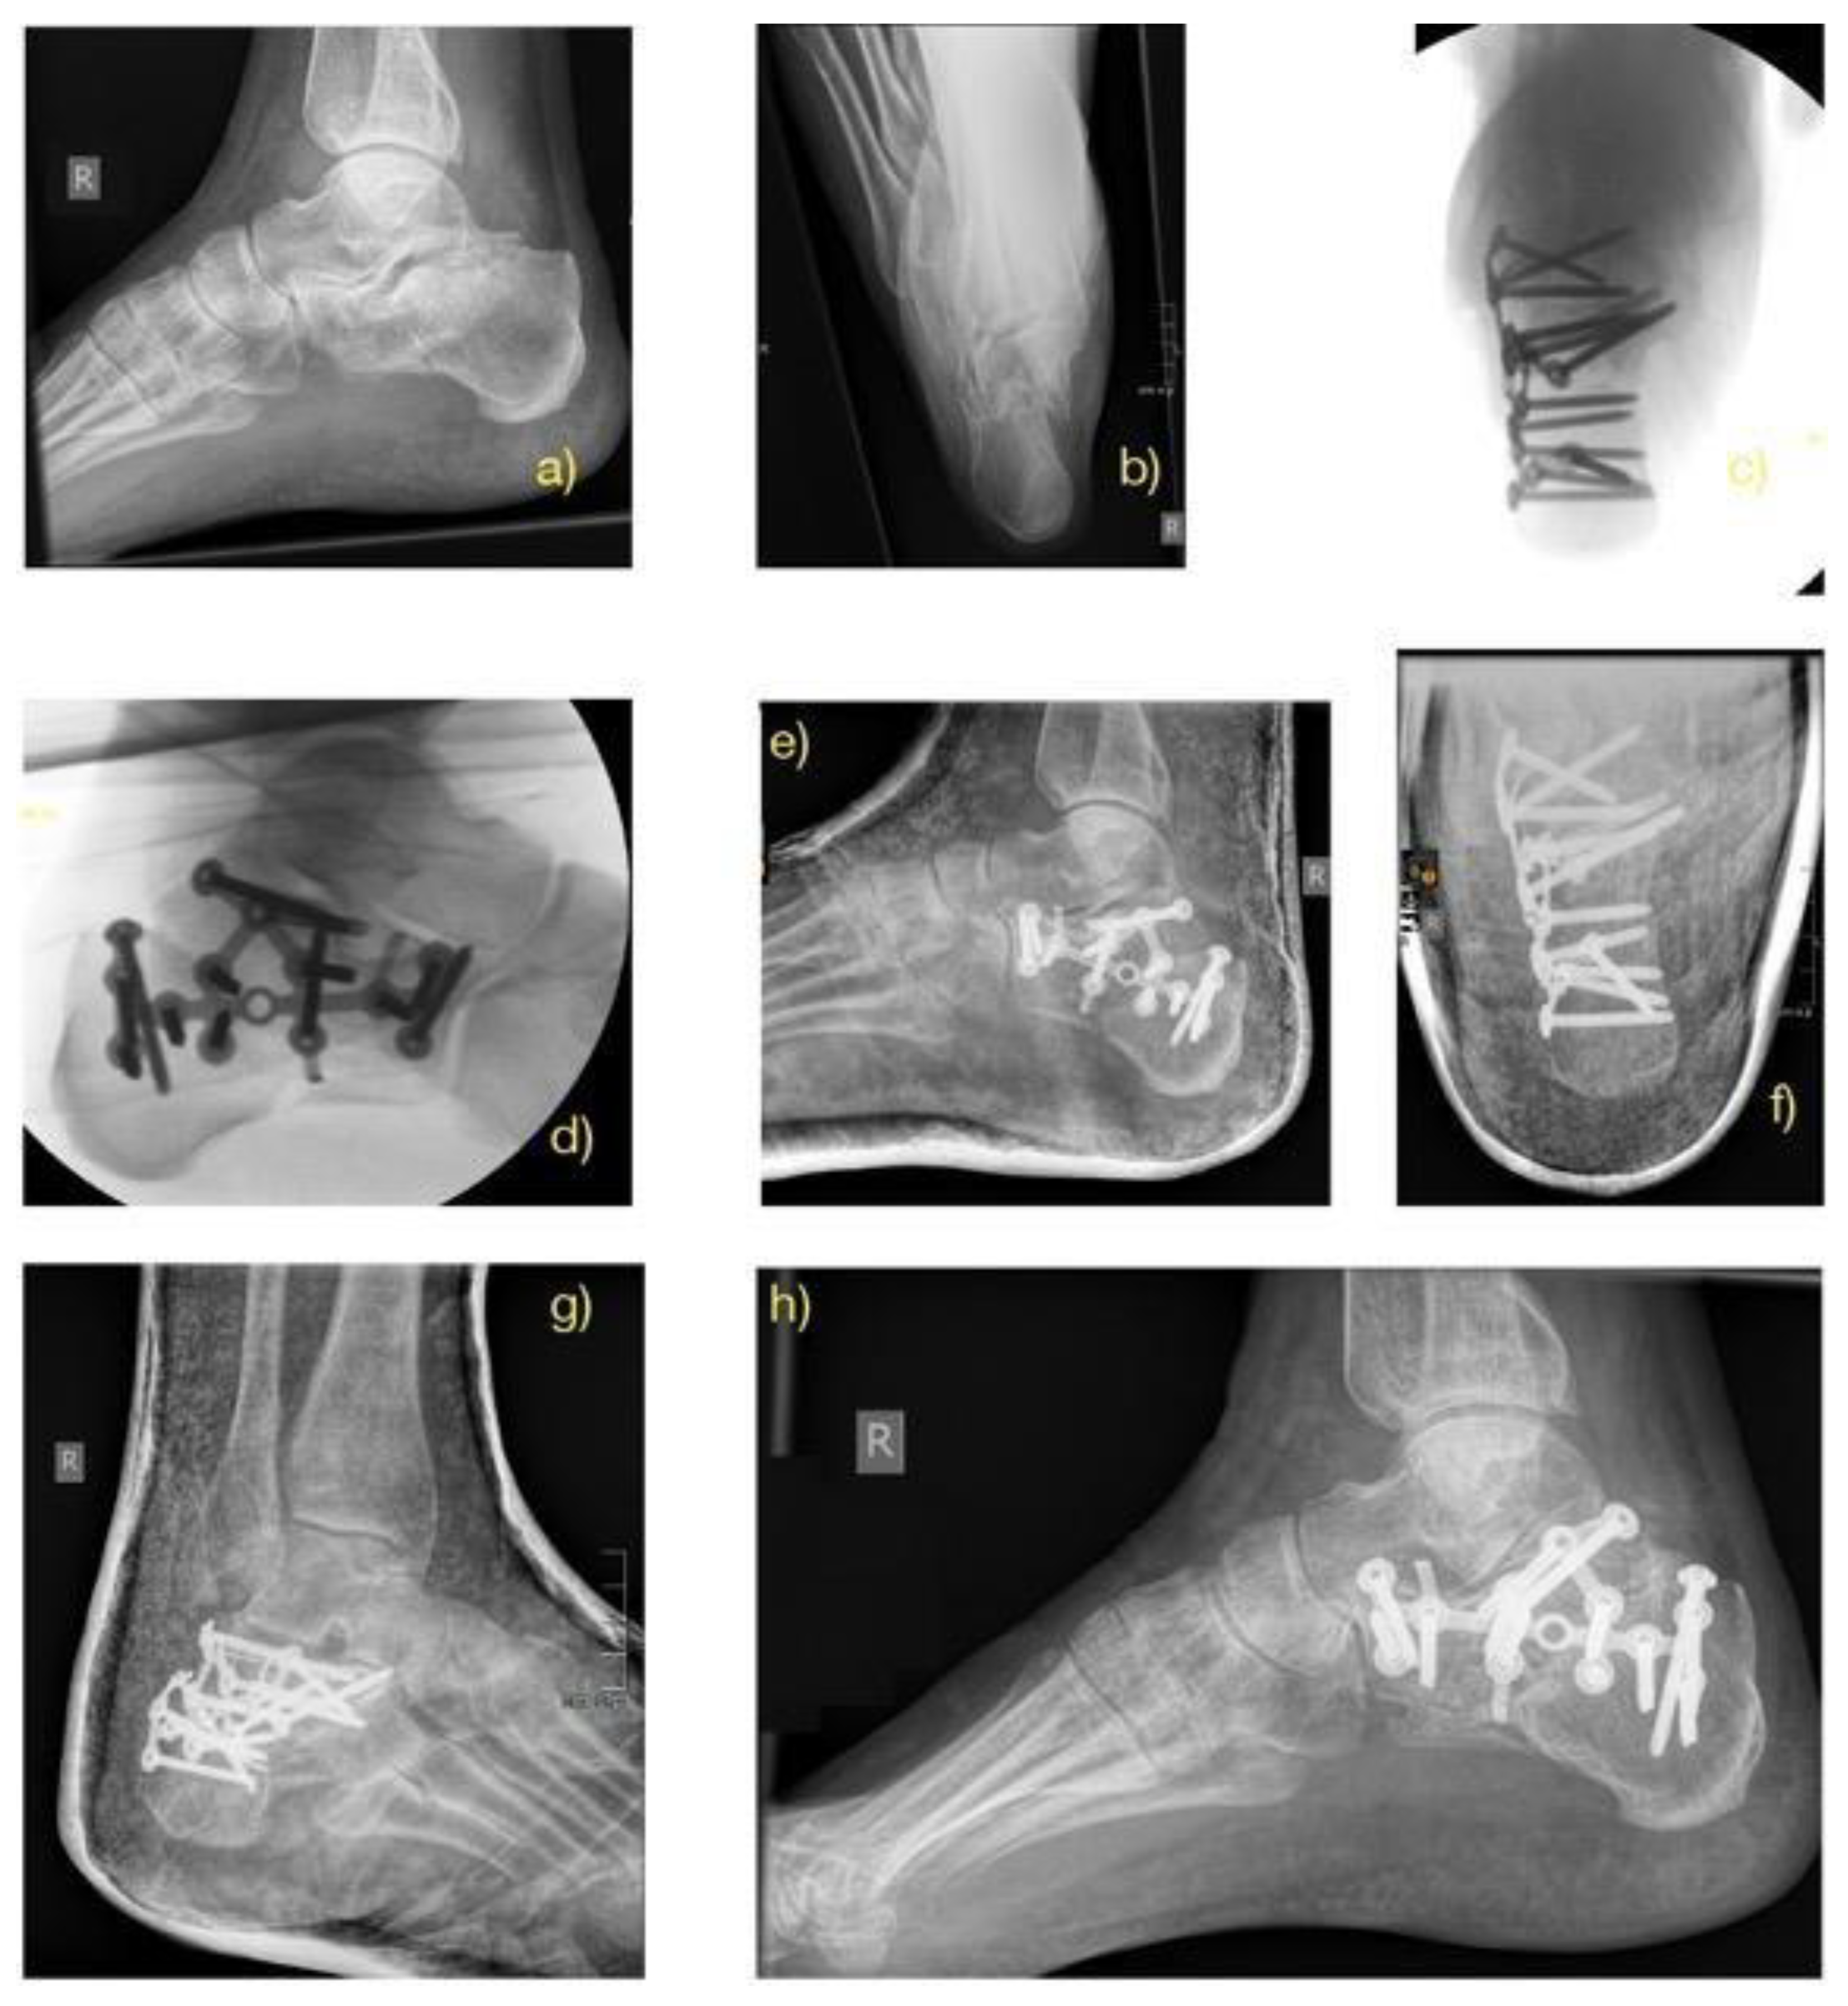

2.2. Treatment Methods